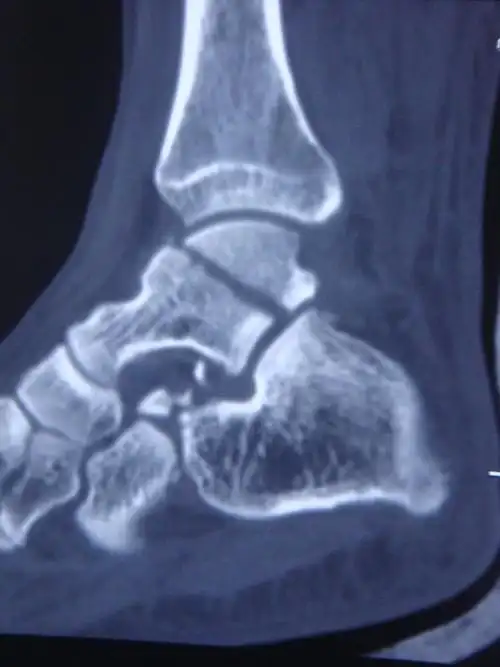

踝关节骨的构成由胫骨,腓骨下端的关节面与距骨滑车构成.

踝关节,由胫骨和腓骨的下端形成深槽,槽内是距骨呈滑车形的上表面.

的二级和三级损伤,应为这种损伤会伴随韧带撕裂,肌肉损伤,距骨突出

以踝部,距骨,跟骨多见.